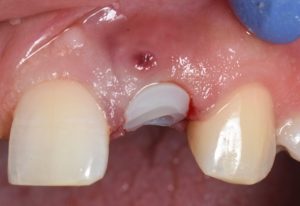

The procedure is presented step by step, including minimally traumatic extraction techniques, immediate implant placement, and fabrication and placement of a customized healing abutment to support peri-implant soft tissue contours. Clinical principles for maintaining papillae, controlling the emergence profile, and optimizing soft tissue healing are highlighted.

- Design and placement of customized healing abutments

- Soft tissue management principles for esthetic implant therapy